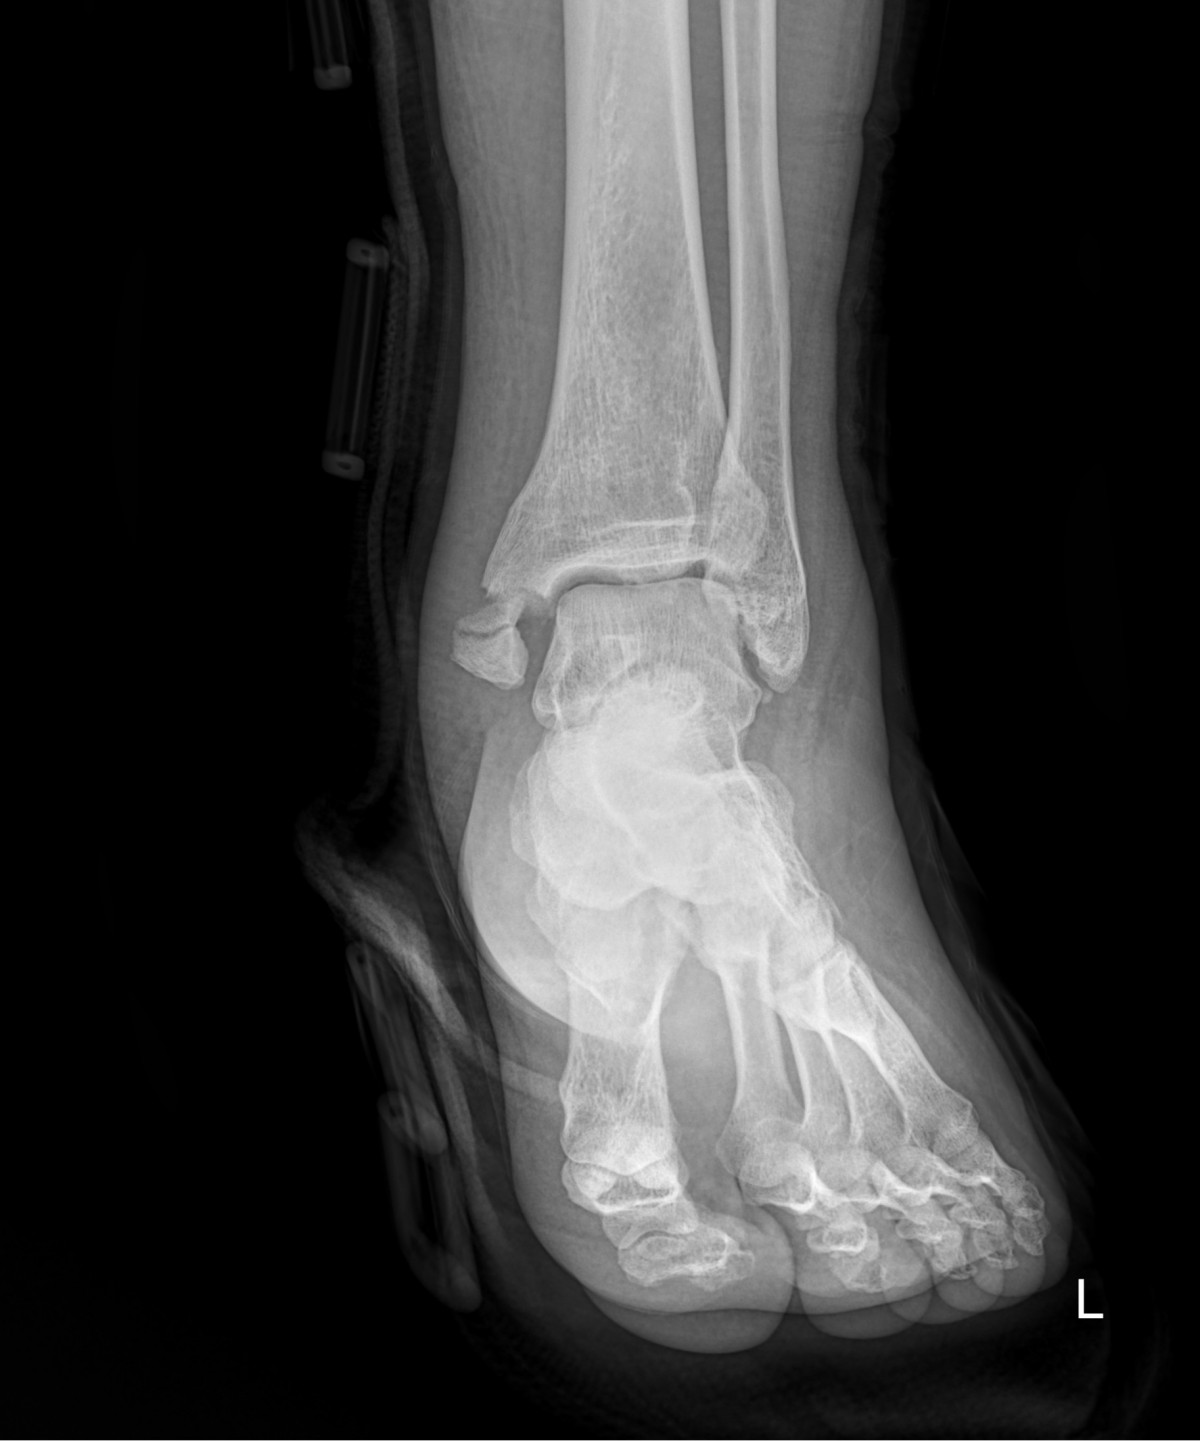

이재상원장님 발목 골절 수술 유현O 환자

dae765e4d9ac96aee867c9d6292d8784_1758002533_4364.jpg